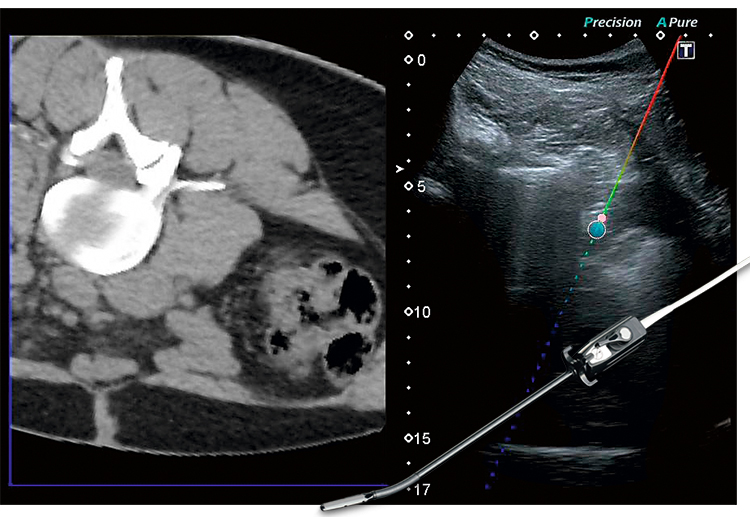

- Smart Fusion или Volume Navigation – эксклюзивная технология, совмещение процесса сканирования УЗИ с изображениями МРТ (с использованием опции DICOM).

Совмещает изображение полученные на КТ и МРТ, с изображением, получаемом в процессе УЗ-диагностики.

Функция Smart Navigation системы Aplio позволяет улучшить точность и повысить безопасность пациента во время проведения абляционных процедур.

Лапароскопический датчик позволяет проводить малоинвазивные процедуры, выполнение биопсий, а также абляции под ультразвуковым контролем.

Технология улучшения визуализации биопсийной иглы BEAM, разработанная корпорацией Canon Medical Systems, в режиме реального времени обеспечивает четкое отображение кончиков игл на эхограмме.

Center Marker - удобный инструмент для сопоставления положения визуального совмещения области интереса на ультразвуковом изображении с соответствующей областью на поверхности кожи и маркером на датчике.

Технология BEAM обеспечивает четкое отображение пункционных игл без необходимости выбирать оптимальный угол сканирования.